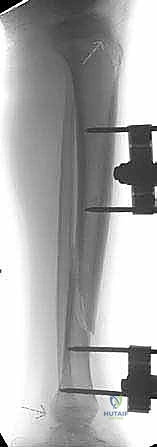

- المثبت الخارجي (External Fixator): يُستخدم في حالات الكسور المفتوحة الشديدة (حيث يوجد تلف في الجلد والعضلات). عبارة عن إطار معدني يوضع خارج الساق ويثبت بمسامير تخترق الجلد إلى العظم.

- استخدام جهاز الأشعة القوسي (C-Arm Fluoroscopy): يُستخدم هذا الجهاز المتطور طوال العملية لتوفير صور أشعة حية ومباشرة، مما يسمح للدكتور هطيف برؤية العظم من الداخل دون الحاجة لشقوق جراحية كبيرة.